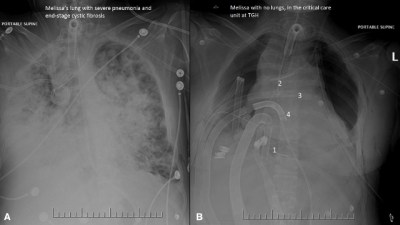

Melissa Benoit lived for 6 days without lungs.(২৯)

A: Melissa’s lung with severe pneumonia and end stage cystric fibrosis. B: Melissa with no lungs in the critical care unit at TGH. Photo courtesy of UHN.(৩০)

ডাক্তাররা আরও জানান, মেলিসার শরীরে প্রতিস্থাপন করার জন্য এমন কাউকে পাওয়া যাচ্ছিল না, যার শরীর থেকে একই সঙ্গে দু’টি ফুসফুস নিয়ে নেওয়া যায়। আর তা হাতে আসার পর, অর্থাৎ ফুসফুস ছাড়া লাইফ সাপোর্টে ৬ দিন থাকার পরই মেলিসার শরীরে ফুসফুস প্রতিস্থাপন করা সম্ভব হয়। আর ওই ৬ দিন ওই রোগীকে তার অকার্যকর হয়ে পড়া দু’টি ফুসফুস ছাড়াই কৃত্রিমভাবে বাঁচিয়ে রাখা হয়েছিল।এরপর নয় ঘণ্টা ধরে ফুসফুস প্রতিস্থাপন করা হয় ওই রোগীর দেহে। ফুসফুস প্রতিস্থাপনের পর এখন সম্পূর্ণ সুস্থ আছেন মেলিসা।